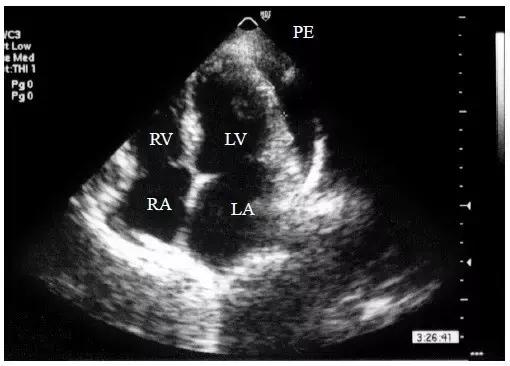

【少量心包积液】

液体仅潴留在左心室后壁和侧壁心包腔内,内径<10mm(图1)。

图1 少量心包积液的二维超声心动图表现

左心室后壁心包腔内少量液性暗区,内径< 10mm